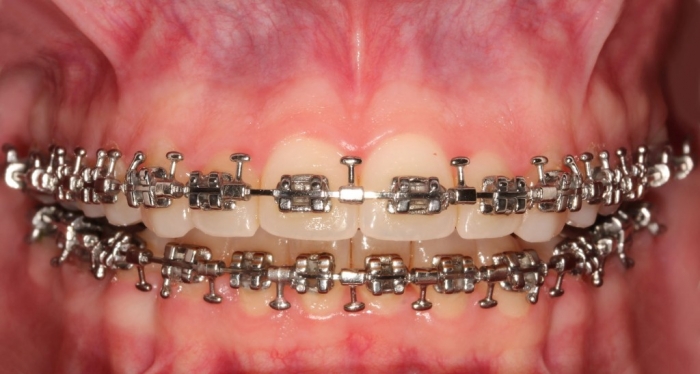

Mordida inicial

Mordida após a cirurgia